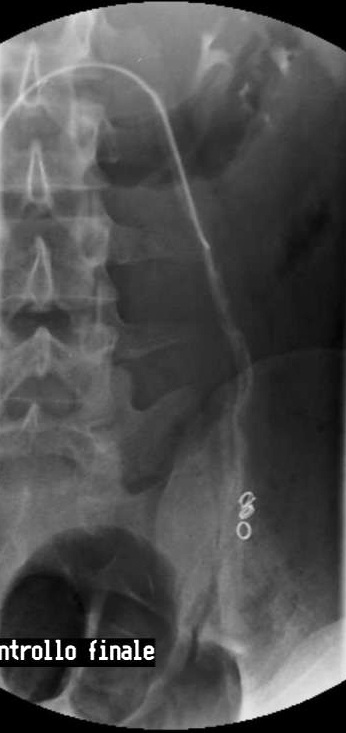

患者处于反Trendelenburg位置,进行左肾静脉造影,以发现睾丸静脉的返流。将导管插入左肾静脉,进行睾丸静脉造影以发现睾丸静脉的返流,以及体循环和门静脉系统的分支显像。使用护罩或充分的平行光,来尽量减少睾丸的暴露。无需对静索静脉曲张直接照相,这样可能会增加性腺接受的放射性剂量。导管进入腹股沟管的部位,因此应避免经阴囊照相。在试图阻断所有可能会引起复发的分支时,推荐使用5-mm和8-mm Gianturco圈(Cook, Inc)(由于其放置容易而且价格便宜)。必须格外小心,避免金属圈的展开部分进入肾静脉或选择直径太小的金属圈,尤其在静脉痉挛时,这样可能会导致金属圈入肺。如果出现静脉痉挛,给予1ml 硝酸甘油液(100µg/ml)缓解痉挛。

由于价格便宜,安全,并且可以容易的在多个位置放置,研究者使用大小为3,5,8和12mm的Gianturco金属圈。一些作者指出金属圈可以引起慢性炎症并导致疼痛,尤其在年轻患者中较为突出。Chomyn报道过从肺内取出金属圈的病例【Chomyn JJ 1991】。有作者使用较新的铂金属圈设计。尽管较为昂贵,但这些金属圈的优点是产生较少的MR伪影。对于老年患者,可能会由于其他原因需要进行另外的矢状面透视。

弹簧栓子+泡沫硬化剂 技术成功率为97.2%【Eric Reiner 2008】 硬化与栓塞比较 硬化治疗导致所有的侧支循环闭塞,甚至我们并没有在静脉造影中看到的。虽然机械阻塞或胶阻塞考虑与外科血管结扎相似。硬化治疗虽然与弹簧栓子或胶相似结果,但没有弹簧栓子移位或胶移位的危险【Iaccarino V 2012】。 Sclerotherapy: Why not? | ||||||||||||||||||||||||||||||||||||||||||||||||||||||||||||||||||||||||||||||||||||||||||||||||||||||||||||||||||||||||||||||||||||||||||||||||||||||||||||||||||||||||||||||||||||||||||||||||||||||||||||||||||||